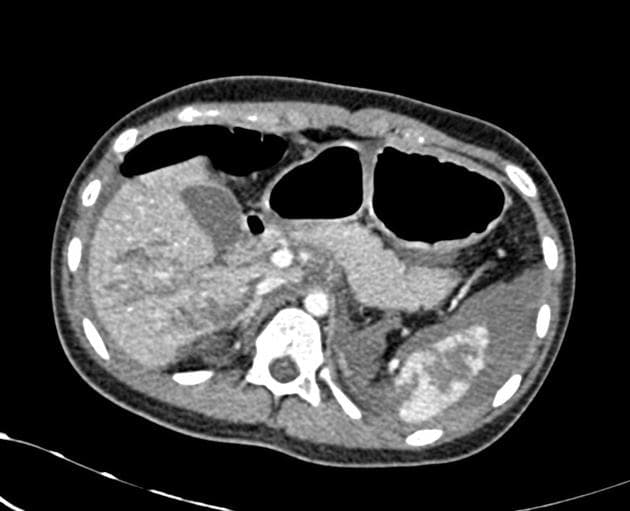

Axial C+ portal venous phase

Chấn thương gan - độ IV theo phân loại AAST

- Ghi nhận một vết rách gan kèm theo huyết khối trong nhu mô gan, ảnh hưởng đến các phân đoạn IV, V và VIII theo phân loại Couinaud, kích thước khoảng 82 x 65 x 82 mm, có điểm chảy máu hoạt động (active bleeding site) bên trong.

- Có một lượng nhỏ huyết khối dưới vỏ (subcapsular hematoma) ở mặt trước gan.

- Chấn thương đụng dập thận phải nghi ngờ (suspected renal contusion) kèm theo huyết khối dưới vỏ (subcapsular hematoma), độ I theo phân loại AAST.

- Dịch tự do (free fluid) có độ cản quang thấp (<10 HU) được quan sát thấy trong ổ bụng chậu.

Hình ảnh học phù hợp với tổn thương gan độ IV theo phân loại AAST, có chảy máu hoạt động (active hemorrhage), kèm theo tổn thương thận phải độ I.